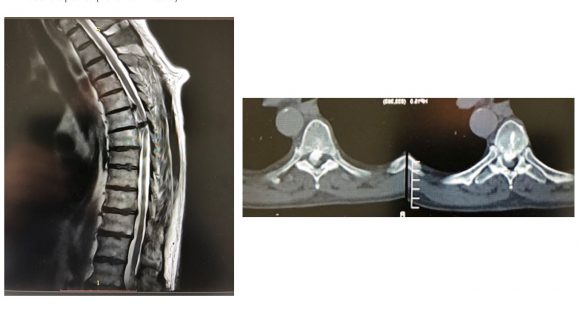

Με την πάροδο του χρόνου οι μεσοσπονδύλιοι δίσκοι μπορεί να υποστούν φθορά και να προβάλουν προς τα πίσω, πιέζοντας το νωτιαίο μυελό και τα νεύρα. Μάλιστα, συχνά, στη θωρακική μοίρα οι δισκοκήλες είναι επασβεστωμένες ή συνοδεύονται από μεγάλα οστεόφυτα (Εικόνα 1)